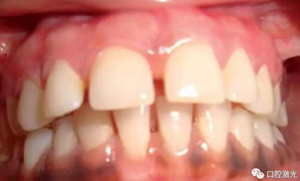

術(shù)后一周

術(shù)后三月